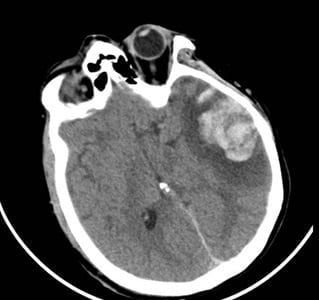

Phim CT não của 2 bệnh nhân

Tại Bệnh viện Nhân dân 115, bệnh nhân G.A nhập viện trong tình trạng hôn mê sâu, phải thở máy nội khí quản. Kết quả chụp CT sọ não cho thấy dập não xuất huyết rải rác nhiều vị trí, phù não lan tỏa nặng, tiên lượng rất dè dặt, nguy cơ tử vong cao. Bệnh nhân được điều trị tích cực tại Đơn vị Hồi sức ngoại khoa, Khoa Gây mê Hồi sức với sự theo dõi sát sao của ê-kíp chuyên môn.

Người mẹ, bà G.N. cũng trong tình trạng rối loạn tri giác, dập não thái dương lượng lớn. Sau hội chẩn kỹ lưỡng, các bác sĩ quyết định lựa chọn phương pháp điều trị bảo tồn nhằm hạn chế tối đa tổn thương thứ phát. Hướng điều trị này cho thấy hiệu quả rõ rệt khi người bệnh dần tỉnh táo, cải thiện khả năng giao tiếp và chức năng ngôn ngữ. Sau 10 ngày điều trị tại Khoa Ngoại thần kinh, bà G.N. hồi phục tốt và được xuất viện.